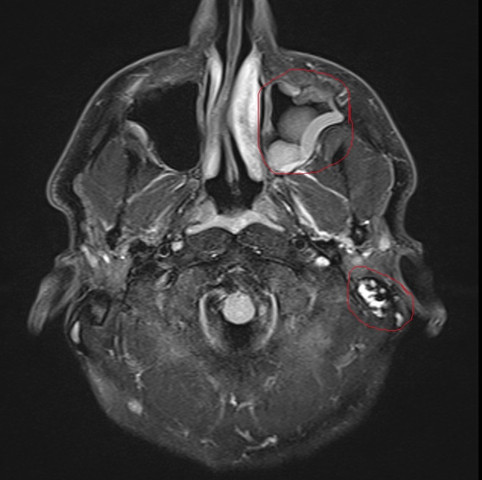

Mrt Bild Vom Kopf Was Ist Das Am Rechten Ohr Nasennebenhohlen